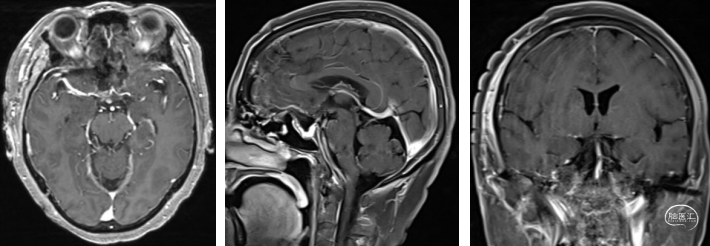

头颅增强核磁:蝶鞍可见片条状异常信号影并向前延伸,长度约33mm,高约14mm,垂体显示不清,视交叉受压,增强后强化明显,局部欠均匀,可见脑膜尾征,考虑为脑膜瘤可能。

经详细术前评估及讨论后,予以全麻下行“右额外侧入路鞍区肿瘤切除术”,手术过程顺利,术中见肿瘤生长至双侧视神经管内,肿瘤包绕颈内动脉,同垂体柄粘连紧密。

术后复查核磁肿瘤切除干净,右眼视力情况较前改善。术后患者出现轻度尿崩,低钠,皮质醇及甲状腺素水平降低,予以对症治疗后好转。

术后核磁:肿瘤切除干净,垂体及垂体柄保留完好,术区无出血。